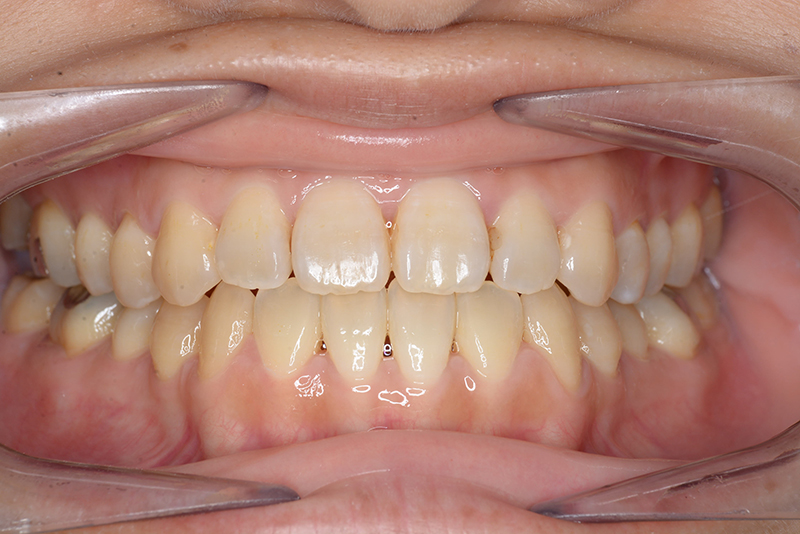

動的治療終了時

FP・IOP

批評・予后 ロウアングルのSkeletal Ⅲ級であり、下顎臼歯は近心傾斜しつつ7遠心部にはアップライトができるスペースがあると判断して、MEAWによる咬合平面の平坦化および可及的な下顎のカウンタークロックワイズローテーションによって改善を行うこととした。治療後には歯列の整直とⅠ級の咬合が得られた。(H30年9月現在で)保定開始4年経過しているが現在も咬合は安定している。